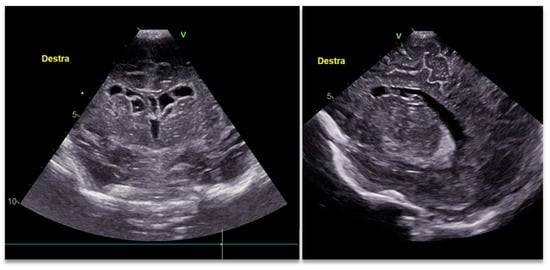

2. Case Report